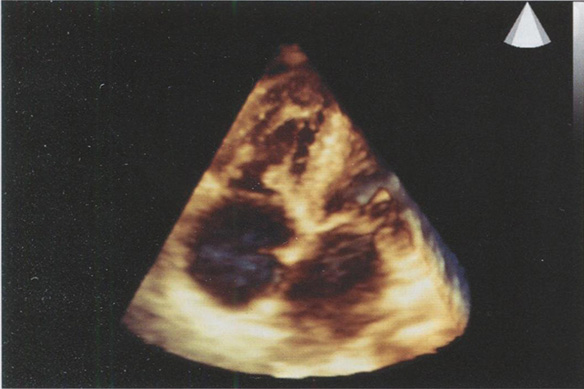

Оценка положения желудочков и предсердий

Необходимо оценить, как расположены левый и правый желудочки по отношению к левому и правому предсердиям. В верхушке правого желудочка имеется модераторный мышечный тяж. Правое фиброзное кольцо в норме смещено в полость правого желудочка до 7 мм. В правое предсердие впадают полые вены и коронарный синус, в левое предсердие - четыре легочные вены (рис. 2.3).

Рис. 2.3. Апикальная четырехкамерная позиция в норме. Модераторный тяж правого желудочка, легочные вены, впадающие в левое предсердие.